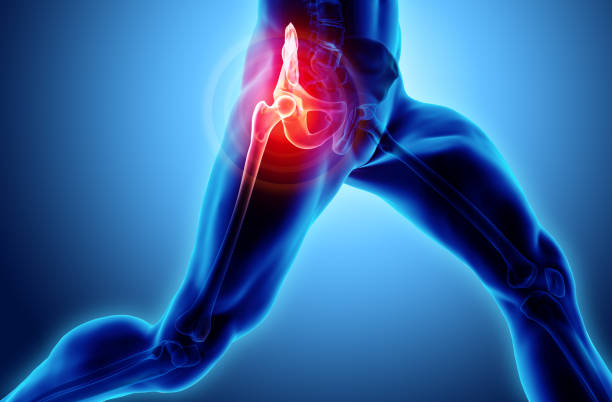

✅고관절 통증 증상 허리디스크? 복합?

고관절 통증의 일반적인 원인 중 하나는 허리디스크입니다. 허리디스크는 허리 부위의 디스크에 문제가 생겨 발생하며, 이로 인해 통증을 겪게 됩니다. 하지만 모든 고관절 통증이 허리디스크로 연결되지는 않습니다. 고관절 주변에도 다양한 원인이 숨어 있을 수 있습니다.

고관절 통증은 종종 단일 원인뿐만 아니라 복합적인 문제에서 비롯됩니다. 이것이 진단과 치료를 어렵게 만들 수 있습니다. 예를 들어, 허리디스크와 함께 관절 주위의 염증, 근육 문제, 혹은 다른 구조적 문제가 동시에 발생할 수 있습니다.